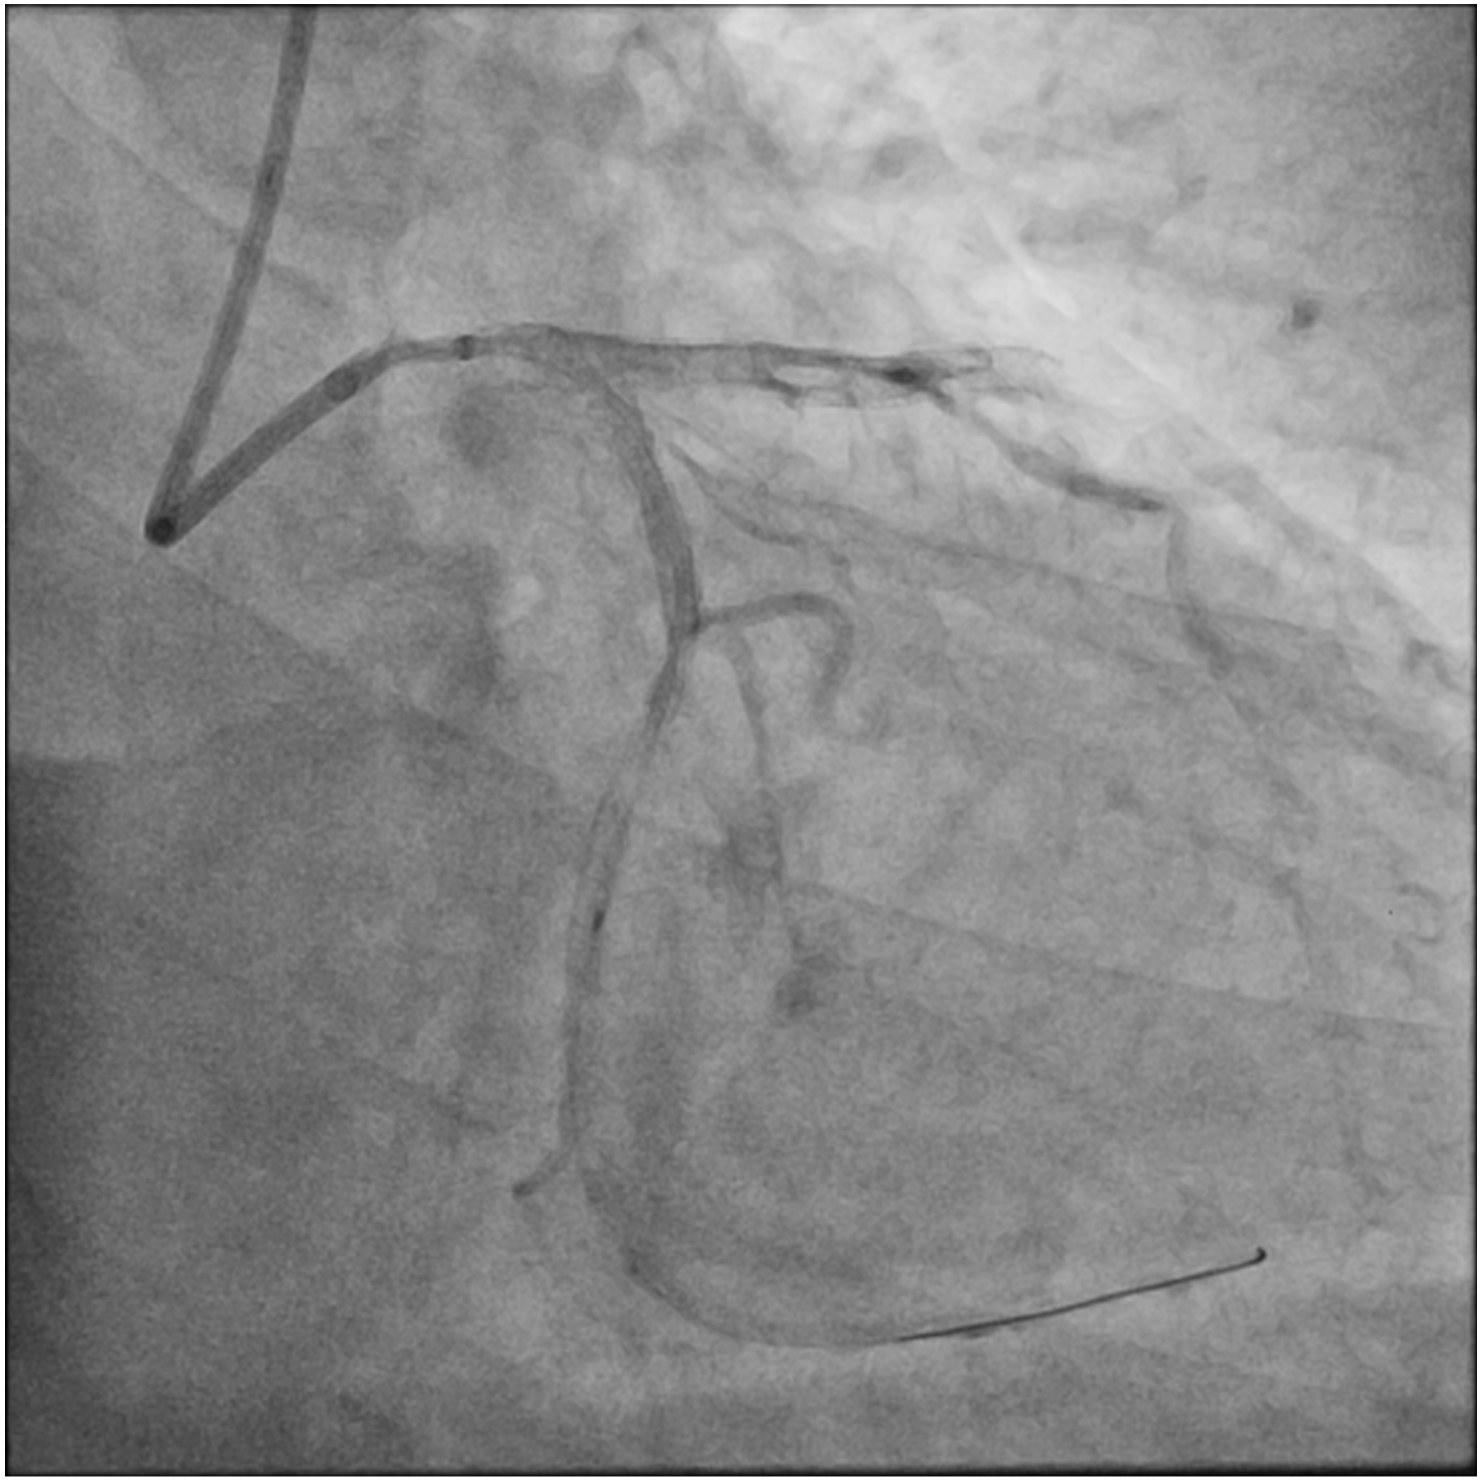

A 71-year-old man who had undergone percutaneous transluminal coronary angioplasty (PTCA) in 2013 was admitted for unstable angina. Coronary angiogram showed 2 de novo lesions at the proximal and distal left circumflex artery (LCX) (Figure 1A). PTCA was performed transradially via a 6-French (Fr) sheath. With a 6-Fr extra-backup 3.5 guide catheter engaging to the left main coronary artery (LM), a 2.5 x 18-mm drug-eluting stent (DES) was delivered to the distal LCX lesion but was inadequate for complete lesion coverage (Figure 1B). During retrieval, the stent was found dislodged at the distal LM bifurcation (Figure 1C).